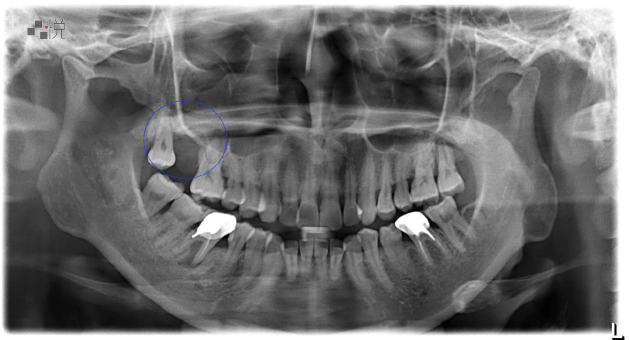

鼻竇炎嚴重蛀牙術後

黃小姐術前 X 光,藍色圈起處為手術完的區域。

(案例提供:黃莞婷醫師)